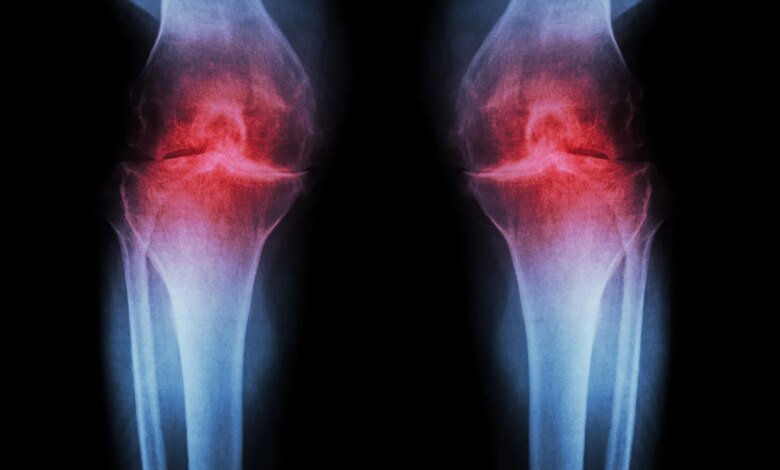

Scientists have found that rheumatoid arthritis (RA) does not begin when pain becomes noticeable. Instead, it starts quietly many years earlier. RA is a serious autoimmune disorder that leads to painful inflammation and damage in the joints.

During the seven-year study, researchers tracked people carrying ACPA antibodies, which are known biomarkers for individuals at-risk for developing RA, and identified previously unknown factors associated with disease development, including widespread inflammation, immune cell dysfunction, and cellular reprogramming.

- Widespread inflammation: Researchers discovered that systemic inflammation was already present throughout the body in at-risk individuals. This wasn’t localized joint inflammation, but rather a body-wide inflammatory state that resembles what’s seen in people with active RA.

- Joint-like inflammation in blood: The researchers identified monocytes (a type of white blood cell) in the bloodstream that were producing high levels of inflammatory molecules. Significantly, these blood cells closely resembled the macrophages found in the inflamed joint tissue of RA patients, suggesting the disease process was already preparing to target joints.